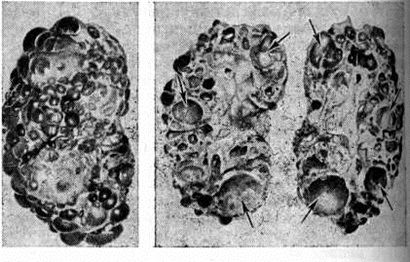

Рис. 1.

Макропрепарат врождённой поликистозной почки (справа почка в разрезе, стрелками указаны полости кист).

Рис. 2.

Фронтальный разрез поликистозной печени (стрелками указаны полости кист).